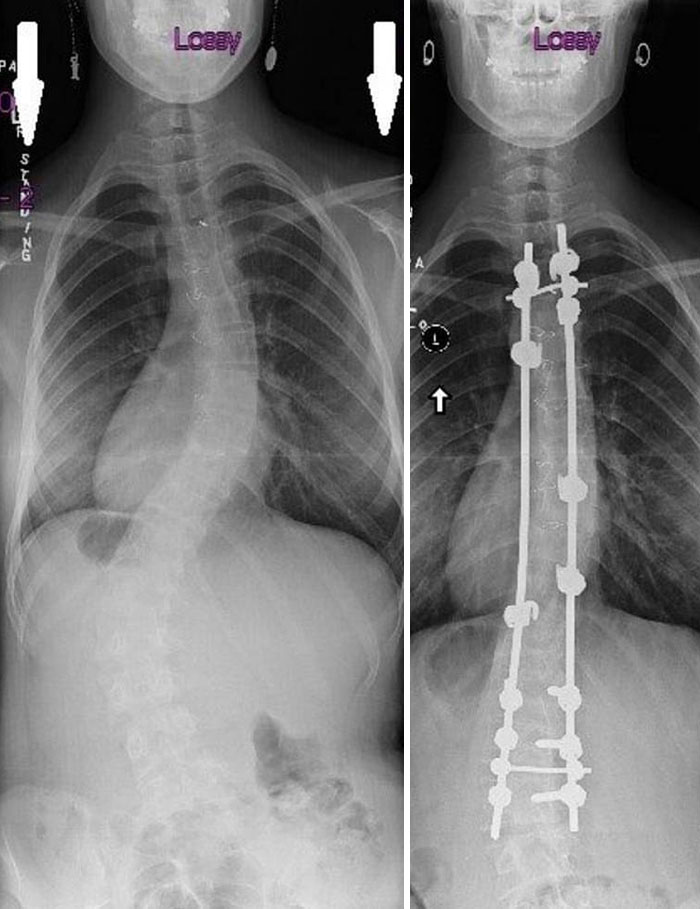

Scoliosis Surgery, Before And After

Can’t imagine how painful and uncomfortable it would be to suffer such significant scoliosis.

X-Rays Before And After Spinal Fusion Surgery For Scoliosis. I Had Surgery At 12 After The Curvature Continued Getting Worse Despite Interventions Being Taken

15 years since surgery and I have no back-related issues. The only issues are caused by the scar tissue from the auto-bone graft from my hip

6 Years Ago Today I Had A Surgery To Straighten Up My Spine, This Is The Before And After Result. I Gained 5 Cm With The Process

X-Rays Of My Spinal Fusion Surgery Before And After